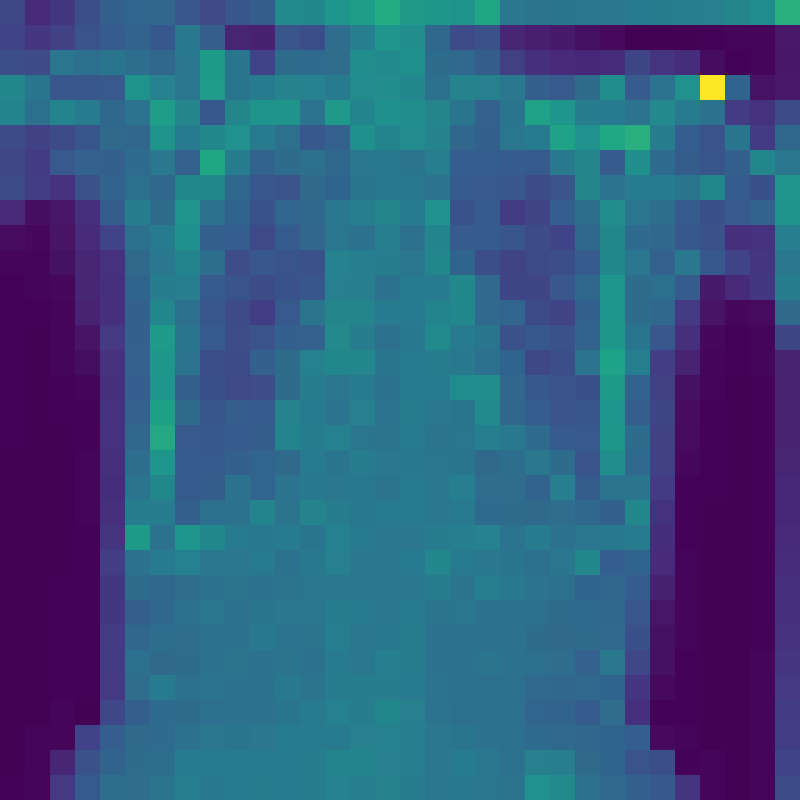

Figure 3: The feature map visualization of the GMSM and QCM modules. (a) Original image; (b) f1subscript𝑓1f_{1}italic_f start_POSTSUBSCRIPT 1 end_POSTSUBSCRIPT in Eq. 1; (c) f2subscript𝑓2f_{2}italic_f start_POSTSUBSCRIPT 2 end_POSTSUBSCRIPT in Eq. 1; (d) f3subscript𝑓3f_{3}italic_f start_POSTSUBSCRIPT 3 end_POSTSUBSCRIPT in Eq. 1; (e) Output of GMSM y𝑦yitalic_y; (f) Output of QCM; (g) Residual between y𝑦yitalic_y and QCM output.

3.2 Visualization of Feature Maps

In this section, we visualize the feature maps of the GMSM and QCM modules, as shown in Figure 3. From Figures 3 to 3, we observe that, during GMSM’s downsampling process, the earlier layers effectively capture the skeletal and organ contours in the X-ray image, while the later layers extract more abstract features. This observation suggests that GMSM progressively extracts key information in a coarse-to-fine manner. As shown in Figure 3, the output from the QCM module closely resembles the feature map of y𝑦yitalic_y in Figure 3. Additionally, the residual map in Figure 3 appears generally darker, indicating the QCM module’s effectiveness in compensating for quantization loss.